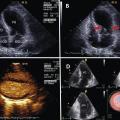

L’échocardiographie faite à l’entrée en USIC recherche la forme évocatrice de piège à poulpe (fig. 2 ) et une éventuelle complication.

Cet examen a un rôle majeur à distance de la phase aiguë pour s’assurer de la récupération complète de la fonction ventriculaire gauche.

L’échocardiographie faite à l’entrée en USIC recherche la forme évocatrice de piège à poulpe (